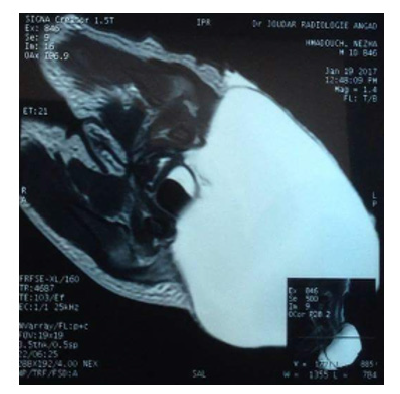

The medullary MRI: A large cloisonné sacro coccygian cyst of type II (teratoma) attached in its internal part to the wall of the rectum without spinal cord injury.

Most CHTs are diagnosed or visible at birth. This is likely due to the fact that the majority of CHTs are predominantly external (total 82%) [13], but in other cases where the external component is absent, the mode of revelation varies according to its prolonged evolution and its locoregional extension which may concern all the structures adjacent to the teratoma. Magnetic Resonance Imaging (MRI) provides the baseline examination that characterizes the nature of the mass, and the links to the muscular and bony structures of the pelvis (upper strait). And to highlight an intrapelvic extension although the relations with the rectum are less visible than with the scanner. It is particularly effective for the study of the spine, so to visualize an intra-spinal extension and/or remove the doubt on meningocele which remains the first differential diagnosis of TSC.